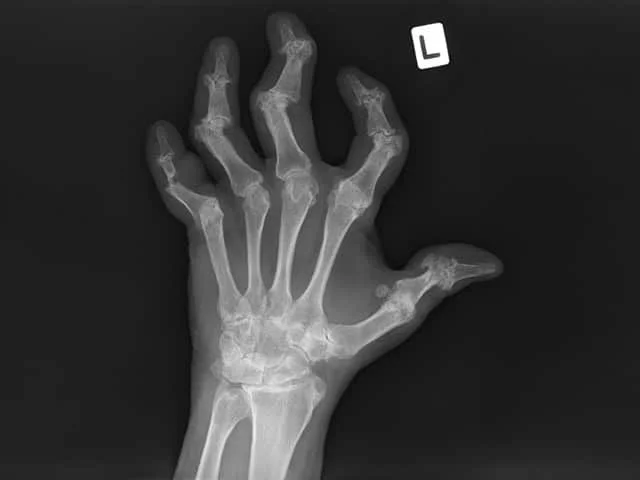

An example of Xray findings of mutilating joints in psoriatic arthritis, which can also occur in rheumatoid arthritis.

Credit: DermNet NZ